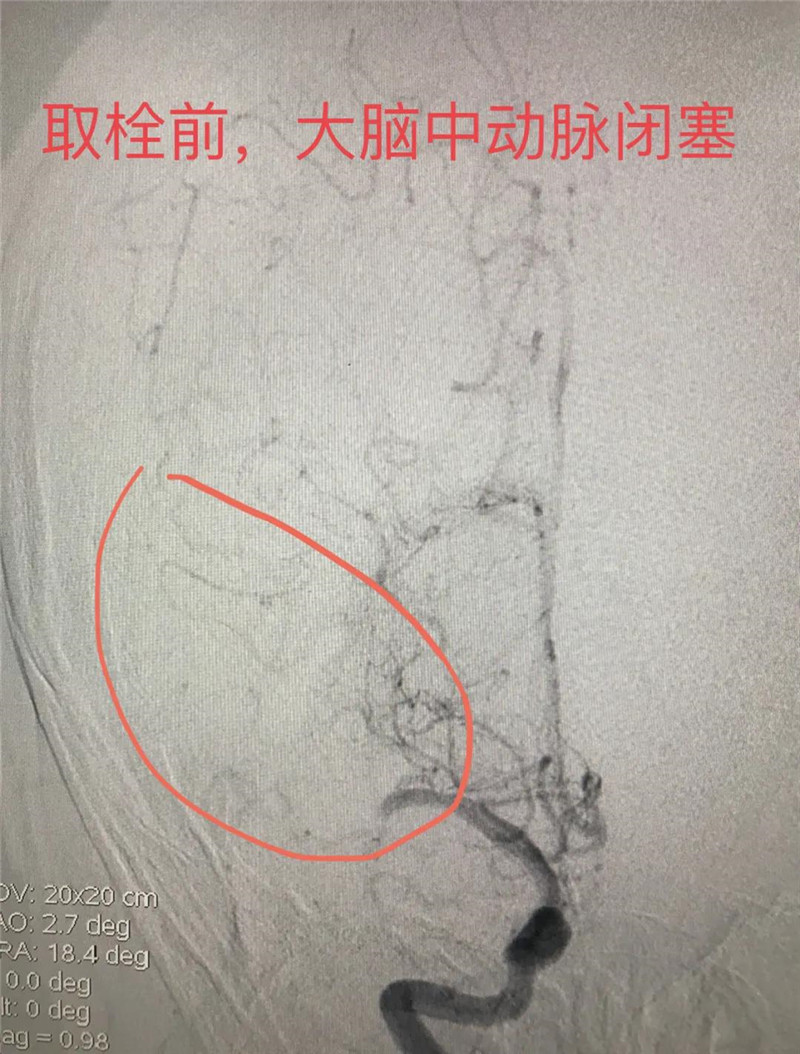

医院立刻开通绿色通道,医学影像科紧急为李叔进行头颅CT检查。结合各类检查结果,李叔疑为右侧大脑急性脑梗塞。急诊科立即请神经内科会诊,神经内科梁文俊副主任医师立刻赶到急诊,查看检查结果后,梁文俊对李叔进行了NIHSS评分(神经功能缺损评分)后,结果为10分、中度中风。结合各类检查结果,考虑李叔的急性脑梗塞应为大血管病变所致,加上李叔出现脑梗塞状况已经三天,已过溶栓时机,必须尽快手术。

获家属同意后,神经内科专家团队在DSA介入室积极配合下开始了取栓手术。穿刺、造影、取栓,手术非常顺利。完成取栓后,李叔当场便清醒过来,之前无法抬起的左手便恢复了自由。随后,李叔被转入神经内科。后续的治疗和康复中,李叔在神经内科医护人员耐心、细致的治疗和护理下康复出院。对于神经内科医护人员的精心治疗,李叔和家人也都十分感动,于是便出现了7月初李叔送锦旗的事情。